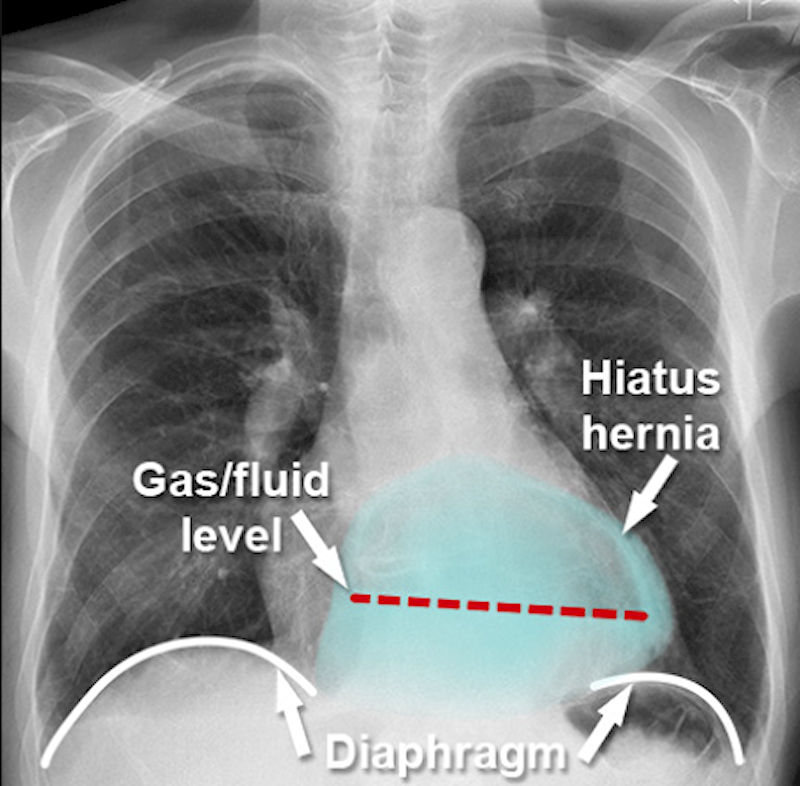

Грыжа пищеводного отверстия диафрагмы (ГПОД) возникает, когда верхняя часть желудка выпячивается через отверстие диафрагмы в грудную клетку. Диафрагма — это мышечный барьер, отделяющий брюшную полость от грудной. Грыжа возникает, когда какой-либо орган или ткань выпячивается через слабое место в тканевом барьере, который обычно его удерживает. Грыжи встречаются часто и грыжи пищеводного отверстия диафрагмы относятся к наиболее распространённым типам.

Рентген с контрастом (барием) — рентген грудной клетки использует для получения чёрно-белых изображений внутренней части грудной полости, где расположен пищевод чтобы определить размер и тип ГПОД.